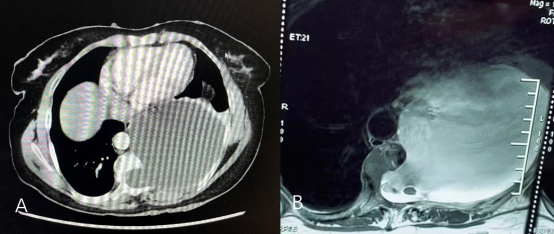

图1:A.患者术前胸部CT显示巨大后纵膈肿瘤. B.术前胸椎核磁显示肿瘤为囊实性,并与椎管内、硬膜内沟通,且合并巨大的脑脊液漏口。

患者为51岁女性,因呼吸困难日益加重,跑遍全国各大医院求医无果。患者及家属抱着一线希望来到我院就诊。经我院胸部CT和胸椎MRI检查显示,患者后纵膈大小约“15cm×14cm×11cm”占位病变,严重压迫心脏以及左侧肺部;该占位为囊实性,与椎管及硬膜内沟通,且合并直径5cm的巨大脑脊液漏口及脊柱裂。